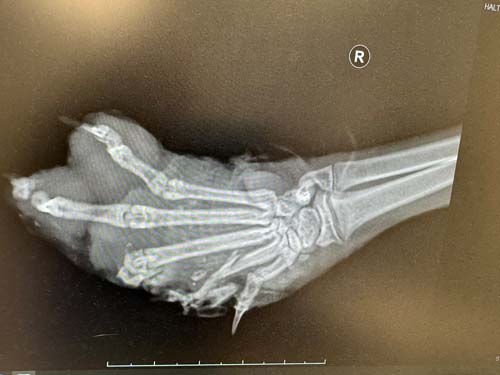

Sein Pfötchen ist zertrümmert, Knochen und Gewebe lagen bereits frei. Der Kleine wurde sofort in die Tierarztpraxis gebracht und notoperiert. Jetzt hoffen wir sehr, dass das Bein gerettet werden kann und keine Amputation nötig ist – ein Versuch ist es allemal wert! 💔 Er ist vermutlich 2025 geborren und wir haben ihn direkt mit kastriert, weil er eh in Narkose musste.